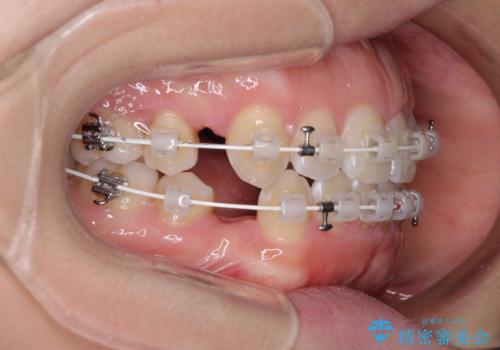

- 矯正装置

- 審美装置

- 治療計画

- 口元の突出感と口の閉じにくさ、前歯のデコボコを気にして来院された患者様です。

上下左右第一小臼歯4本を抜歯し、ワイヤー装置にて口元を引っ込めるよう矯正治療を行うこととしました。